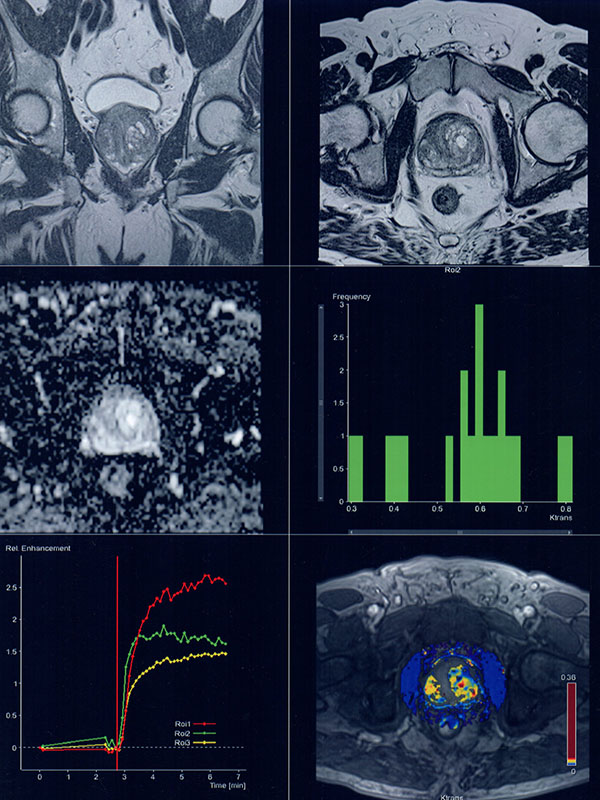

- Estudios de próstata con análisis de las lesiones de diferente naturaleza

- Estudio de alta resolución del recto incluyendo “Difusión”.